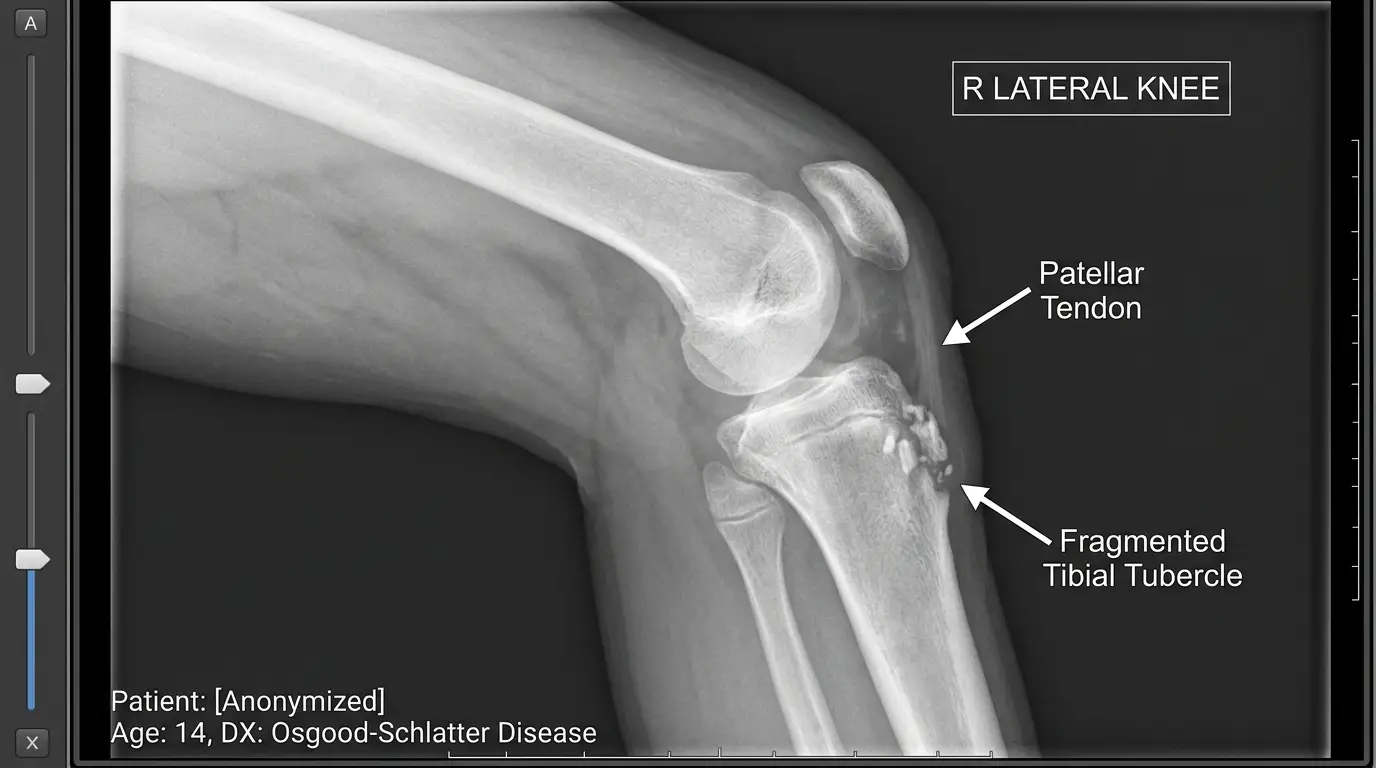

인간의 무릎 구조를 보면, 허벅지 앞쪽의 거대한 근육인 대퇴사두근이 무릎덮개뼈(슬개골)를 지나 슬개건(Patellar tendon)이라는 힘줄의 형태로 정강이뼈 상단의 약간 튀어나온 부위(경골 결절)에 부착됩니다. 문제는 키가 급격하게 자라는 10~15세의 급성장기에 발생합니다. 뼈는 하루가 다르게 길어지는데, 근육과 힘줄의 성장 속도는 이를 따라가지 못합니다. 이 상태에서 아이들이 축구를 하며 공을 강하게 차거나, 농구를 하며 점프를 반복하게 되면 어떻게 될까요? 짧고 타이트해진 대퇴사두근이 정강이뼈 부착부를 지속적으로 강하게 잡아당기게 됩니다.

성인이라면 뼈가 단단해서 버티겠지만, 청소년기의 경골 결절은 아직 연골 상태이거나 뼈가 완전히 굳지 않은 성장판 상태입니다. 강력한 견인력(당기는 힘)에 의해 이 연골 부위가 미세하게 뜯어지고 붓는 견열 골연골염(Traction apophysitis)이 발생하게 되는 것이죠. 이것이 바로 무릎 아래가 볼록하게 튀어나오고 누르면 극심한 통증을 유발하는 오스굿씨병의 병태생리입니다. 다행인 점은 대부분 성장이 끝나고 성장판이 닫히면서 뼈가 단단해지면 통증 자체는 자연스럽게 사라진다는 것입니다. 튀어나온 뼈는 성인이 되어서도 평생 흔적처럼 남지만, 일상적인 보행이나 가벼운 운동에는 지장을 주지 않는 경우가 절대다수입니다. 그니까요, 외관상으로는 심각해 보여도 의학적으로는 예후가 매우 좋은 ‘착한(?)’ 질환에 속합니다.

반면, 오스굿씨병은 앞서 설명했듯이 무릎 관절 내부의 인대나 연골이 손상된 것이 아닙니다. 관절 바깥쪽 정강이뼈 표면에 위치한 부착부의 뼈가 자라난 ‘구조적 변형’에 가깝습니다. 무릎을 굽히고 펴는 관절의 가동 범위(ROM)에 치명적인 제한을 주지도 않으며, 체중을 지지하지 못하게 만드는 질환도 아닙니다. 따라서 군의관이 엑스레이를 확인하고 오스굿씨병 소견(경골 결절의 비대 및 유리체 존재)을 발견하더라도, 이는 활동성 통증 증후군으로 간주되어 신체 등급을 낮출 만한 법적 근거가 되지 못합니다.